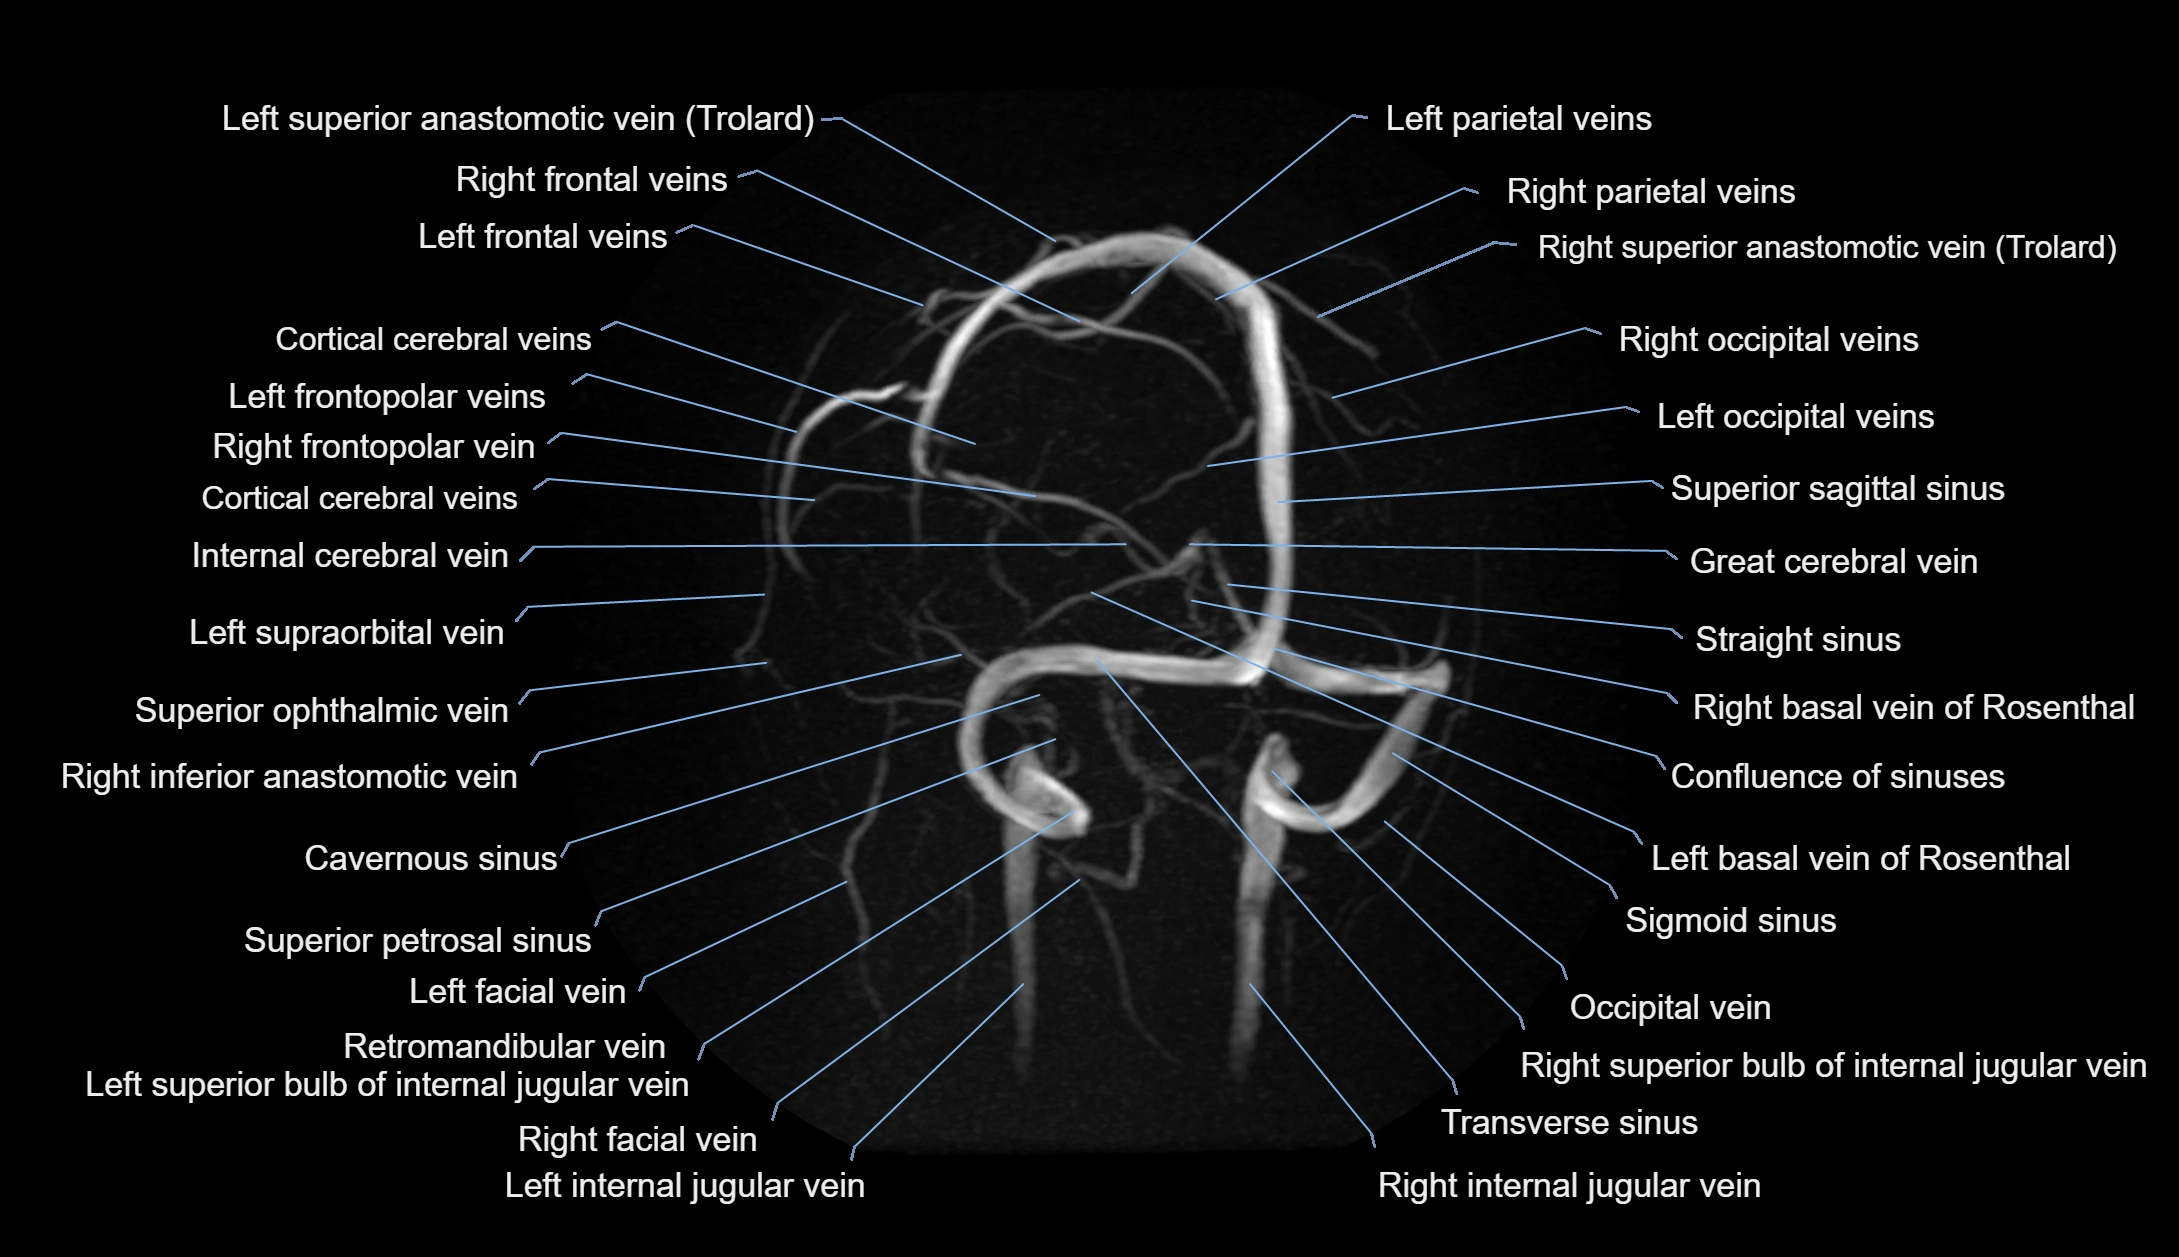

MR Venography (MRV):

• Time-of-flight (TOF) or contrast-enhanced MRV shows the angular vein as a bright enhancing venous channel

• Clearly demonstrates its continuity with the facial vein and superior ophthalmic vein

• MRV is highly useful in evaluating thrombosis, venous obstruction, or collateral venous drainage

MRI images